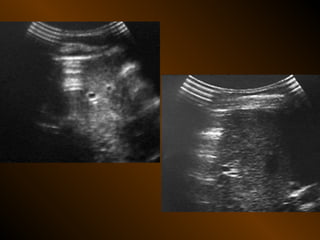

TỤ DỊCH TRONG PHÚC MẠC

• X QUANG QUY ƯỚC

– Trong tiểu khung

– Dọc hai bên hông

– Giữa bụng

• SIÊU ÂM

– Phản âm trống, chuyển dịch

– Lượng ít

– Bản chất dịch

• X QUANG CẮT LỚP ĐIỆN TOÁN

– Mật độ

– Vị trí

– Nguyên nhân

TỤ DỊCH KHU TRÚ

– Tụ dịch ? – khối u ?

– Phản âm, chất chứa, vỏ bọc ?

– Mật độ, bắt cản quang ?